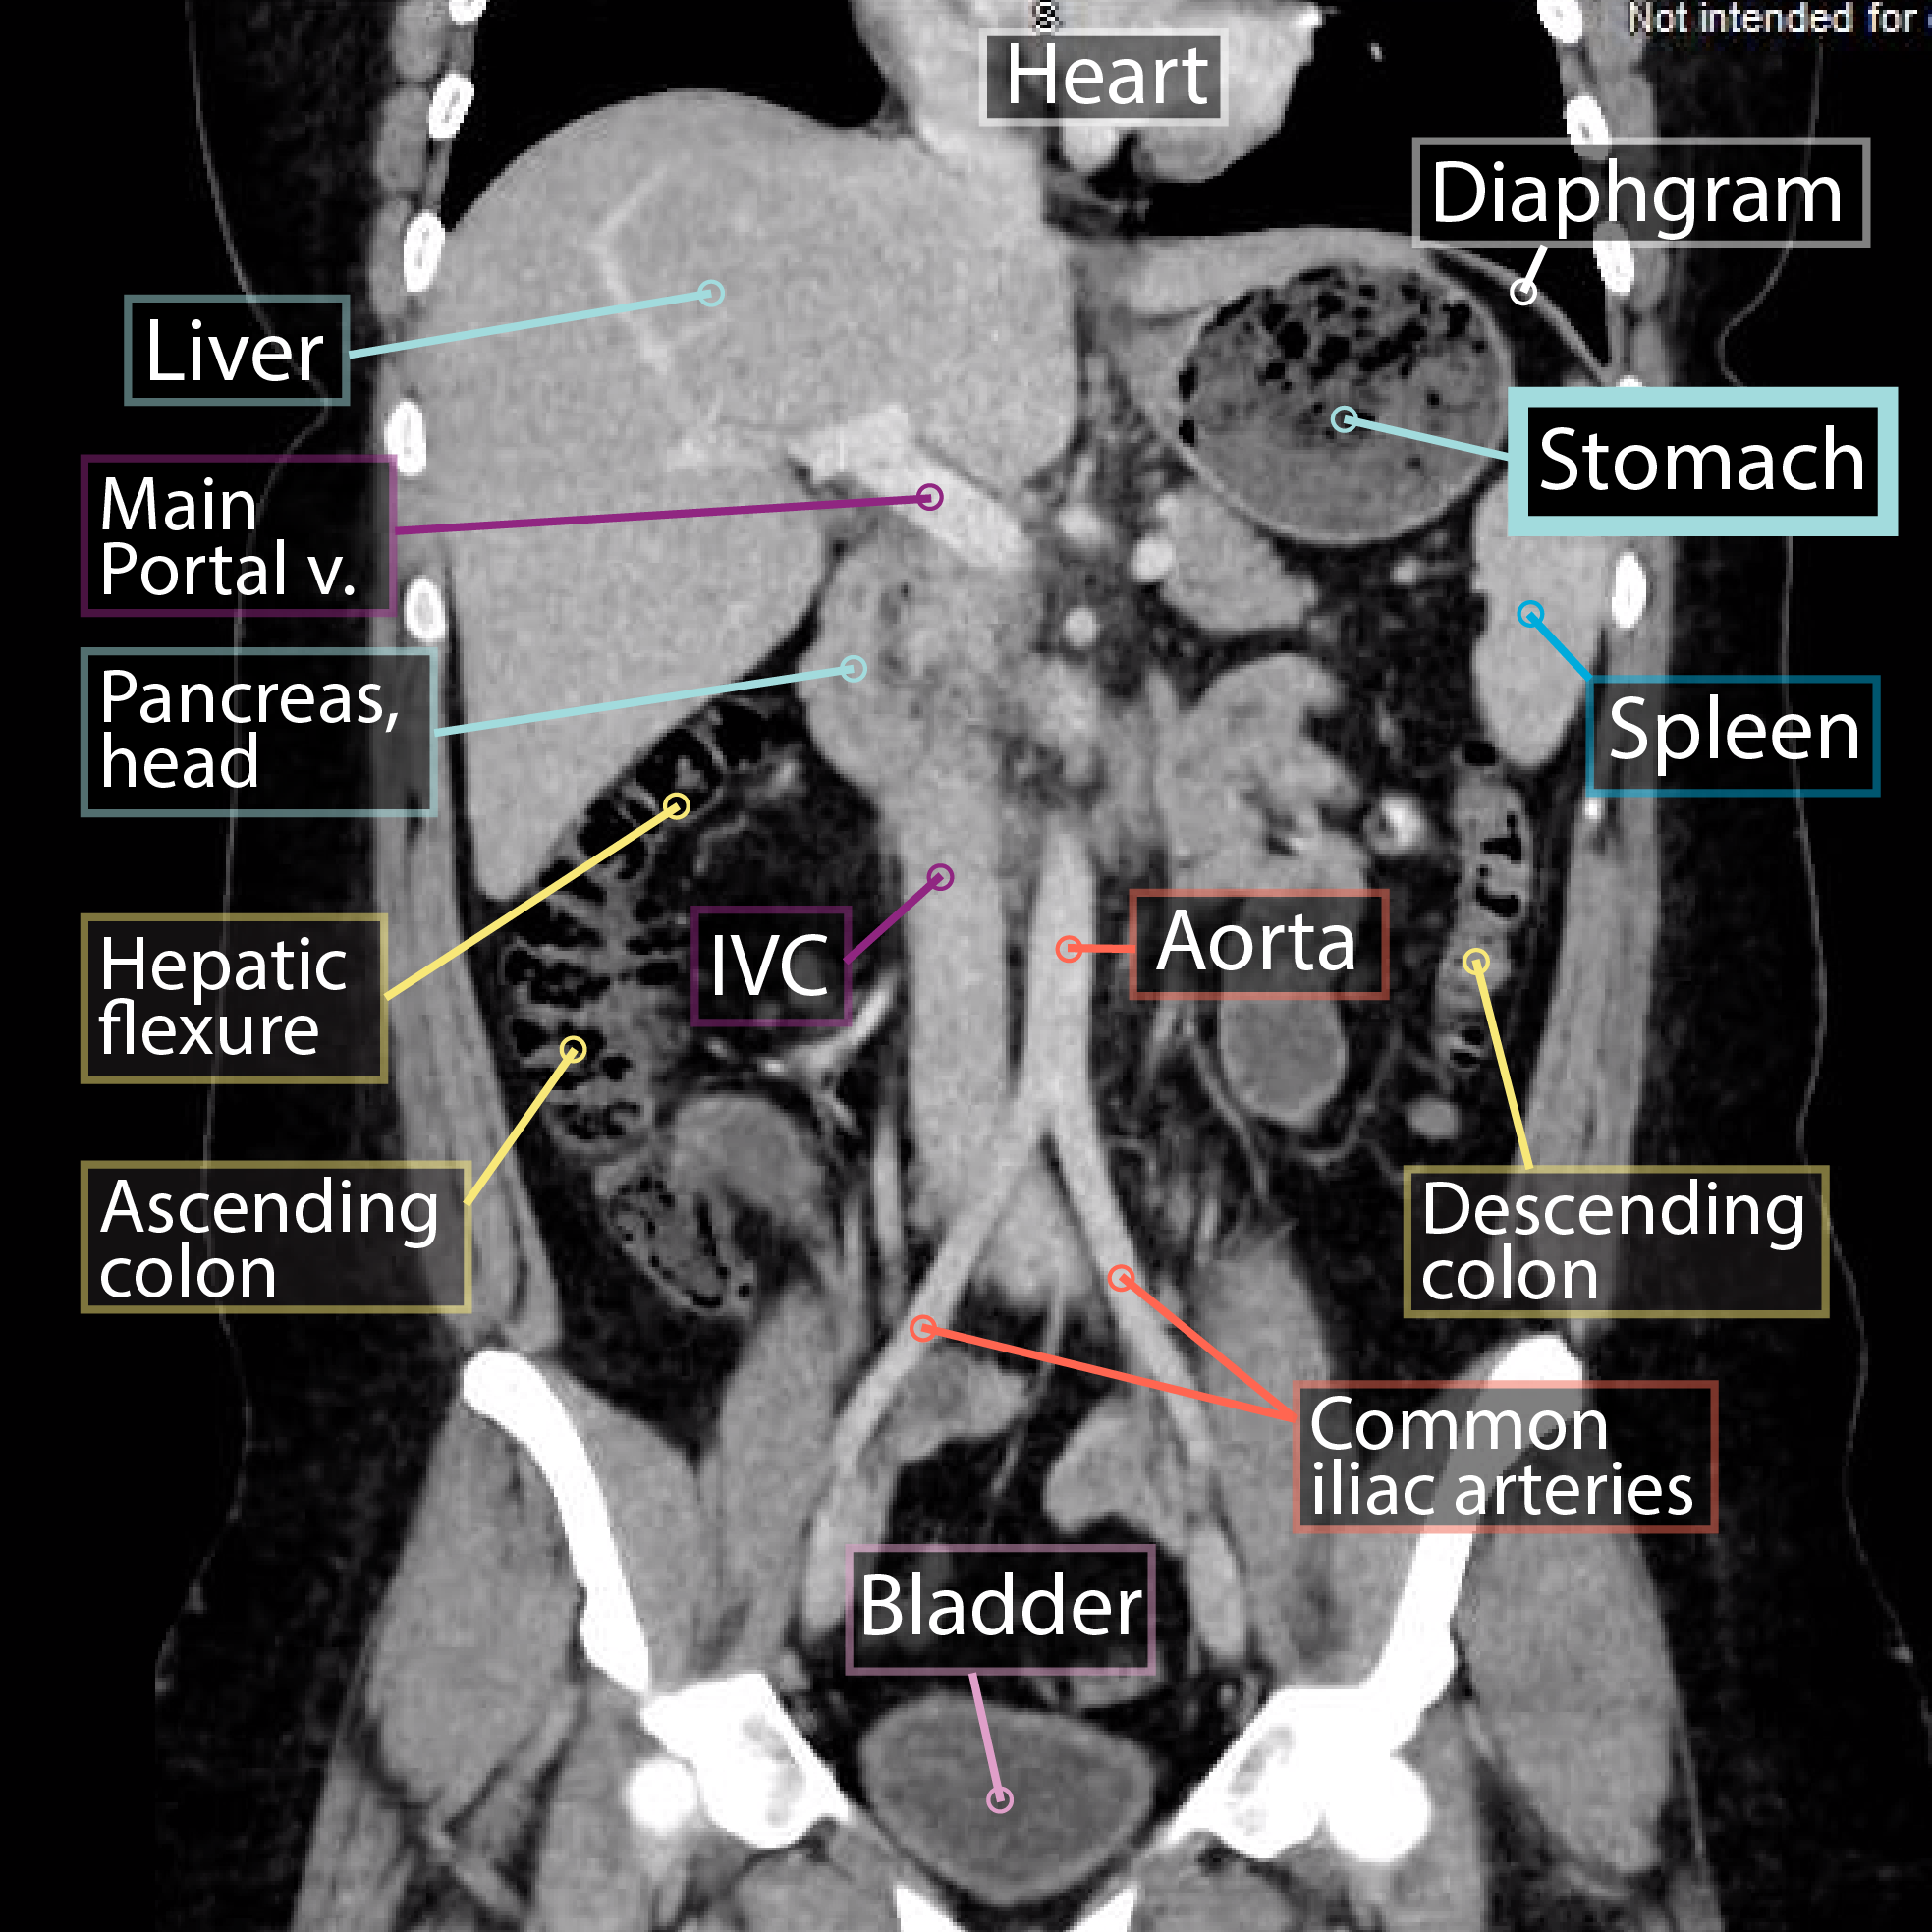

Stomach Imaging